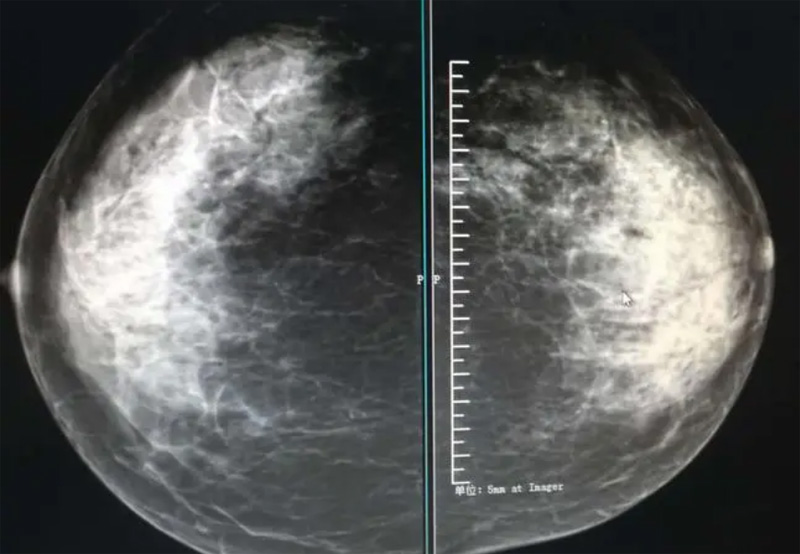

乳腺DR攝影體位有頭尾位及內(nèi)外側(cè)斜位,乳房在片子的中央,乳頭切線位,可見小部分胸大肌,內(nèi)側(cè)乳腺組織應(yīng)全部包括在片中,外側(cè)乳腺組織盡可能包括在片中。一張好的MLO位圖像顯示如下:乳房被推向前上,乳腺實質(zhì)充分展開,胸大肌可見,較松弛,下緣達(dá)到乳頭水平,乳頭在切線位,部分腹壁包括在片中,但與下部乳腺分開,絕大部分乳腺實質(zhì)顯示在片中。乳腺組織外緣可見乳頭的輪廓;乳腺后方的脂肪組織被很好地顯示出來,乳房無皺褶。對于CC位及MLO位顯示不良或未包全的乳腺實質(zhì),可以根據(jù)病灶位置的不同選擇以下體位:外內(nèi)側(cè)位(LM)、內(nèi)外側(cè)位(ML)、內(nèi)側(cè)頭尾軸位(MCC)、外側(cè)頭尾軸位(LCC),尾葉位(CLEO)及乳溝位。在臨床實踐中,對于常規(guī)體位上發(fā)現(xiàn)的異常改變,可以進(jìn)一步采取一些特殊的攝影技術(shù),包括局部加壓攝影、放大攝影或局部加壓放大攝影技術(shù)。

2、規(guī)范觀圖程序:屏幕軟閱讀或在專用日光觀片燈下膠片閱讀,后者應(yīng)同時準(zhǔn)備白熾強(qiáng)光燈及觀片放大鏡。注意雙側(cè)乳腺配對觀察,推薦雙眼橫向掃描,進(jìn)行雙乳相同部位圖像比較分析。

3、乳腺實質(zhì)背景的確定:觀察乳腺實質(zhì)與脂肪的構(gòu)成比例,了解乳腺實質(zhì)類型,以判斷對某些乳腺攝影征象敏感性的影響,有利于確定乳腺攝影對疾病的診斷價值。

必須指出的是,美國放射學(xué)會提出的乳腺影像報告和數(shù)據(jù)系統(tǒng)(Breast Imaging Reporting and Data System, BI-RADS)將乳腺分為4型:脂肪型(乳腺內(nèi)幾乎全部為脂肪組織,腺體組織占25%以下)、少量腺體型(乳腺內(nèi)散在腺體組織,大約占25%~50%)、多量腺體型(乳腺呈不均勻致密表現(xiàn),腺體組織大約占51%~75%)、致密型(乳腺組織非常致密,腺體組織占75%以上)。這種分型的主要意義在于說明X線對不同乳腺類型中病變檢出的敏感性不同,對發(fā)生在脂肪型乳腺中病變的檢出率很高,而對發(fā)生在致密型乳腺中病變的檢出率則有所降低,臨床醫(yī)師了解這一點(diǎn)很重要。